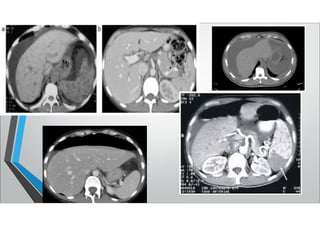

T.A.CABDOMENY PELVIS

• CARACTERÍSTICAS:

• 98% ESPECIFICIDAD En heridas laterales o posteriores

• COSTOSO Búsqueda de lesiones colonicas

• SITRASLADO Comparable al examen físico seriado

• REPETIBLE

• EVALUA MAL

DIAFRAGMA,

INTEST. DELGADOY PANCREAS

T.A.CABDOMENY PELVIS • CARACTERÍSTICAS: •98% ESPECIFICIDAD En heridas laterales o posteriores • COSTOSO Búsqueda de lesiones colonicas • SITRASLADO Comparable al examen físico seriado • REPETIBLE • EVALUA MAL DIAFRAGMA, INTEST. DELGADOY PANCREAS